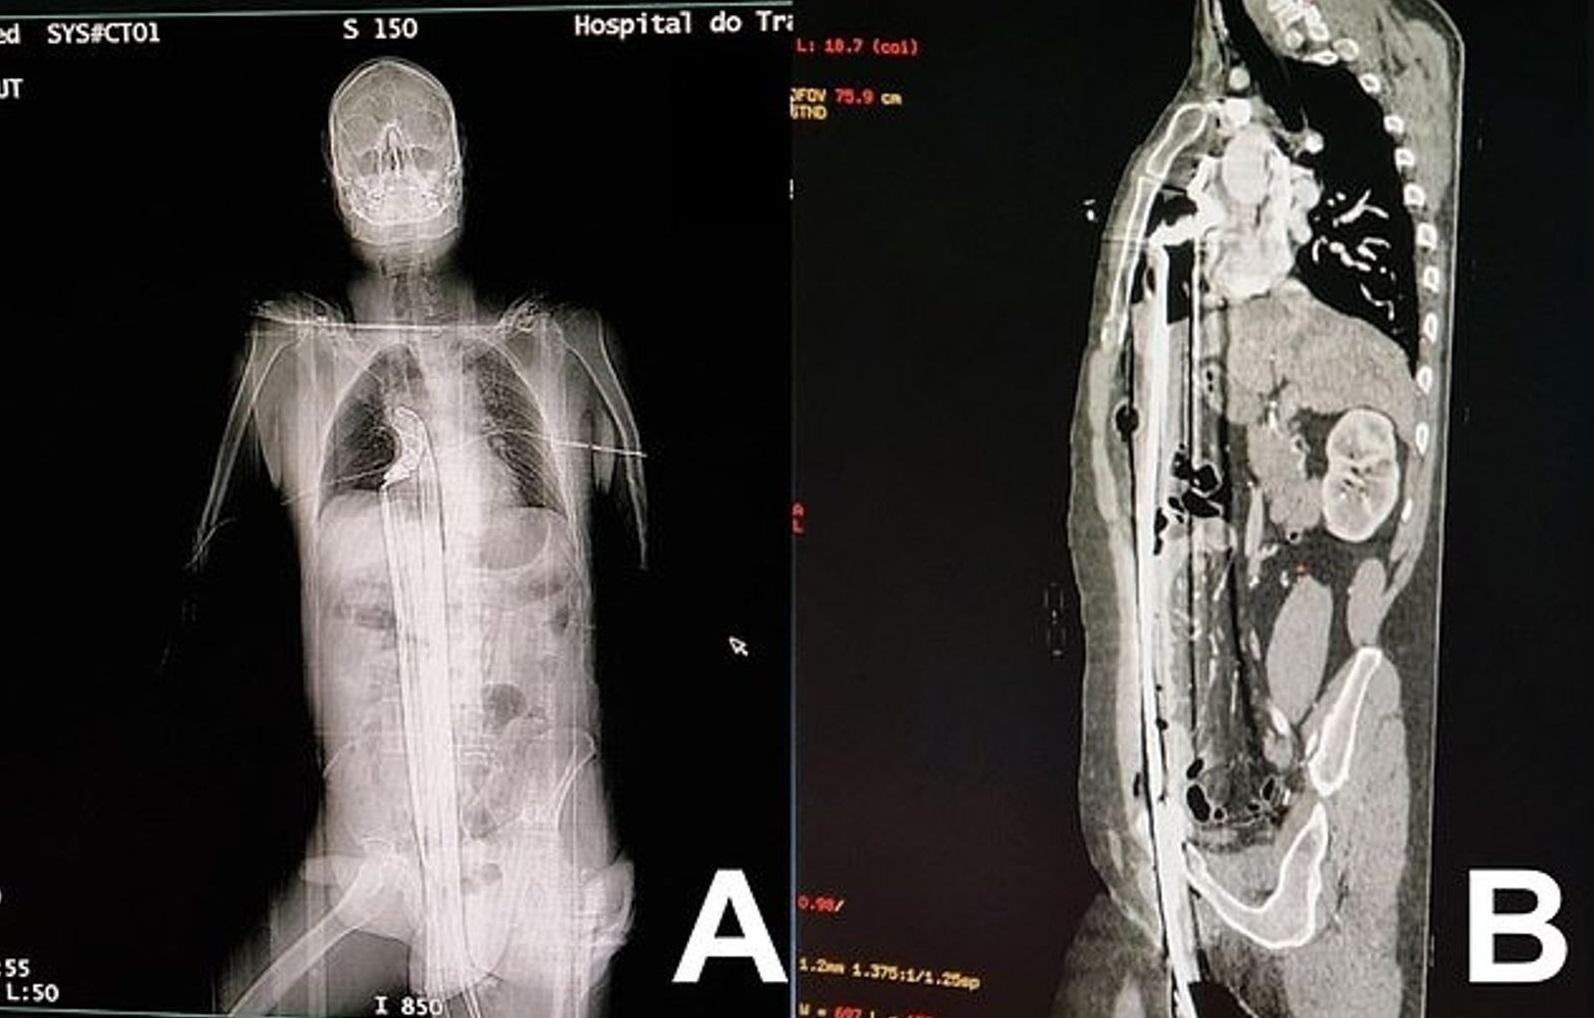

救護員把蓬猜送院,神奇的是,子彈擊中他胸前配戴的佛牌後停住,佛牌擋了子彈而變形凹陷。警員在地上找到佛牌,子彈剛好卡在上面。報道指,佛牌上刻有佛統府蘇旺寺已故住持的肖像。蓬猜左邊胸口因子彈撞擊力受傷,所幸沒有性命危險。